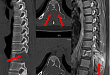

2021.05.06 花季少女脊椎长瘤,绵阳市第三人民医院「皇冠」手术「瘤」去病除

不明原因的腰背部反复疼痛,双下肢麻木、乏力,行走不稳,甚至摔倒……16 岁的花季少女小杜(化名)这段时间被怪病折磨着,最终在绵阳市第三人民医院疼痛科·脊柱外科得到了有效治疗。疼痛科·脊柱外科医生结合小